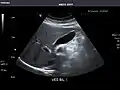

Kidneys: Right and left kidneys measure 11.5 cm and 12 cm in length respectively. No hydronephrosis. Small left lower pole kidney cyst.

Right kidney

Left kidney